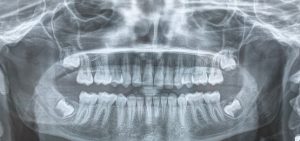

Top 10 des questions médicales les plus posées à Chalons-en-champagne :

- #1 - Pourquoi certaines allergies vont et viennent ?

- #2 - À quels problèmes de santé les bébés prématurés sont-ils confrontés ?

- #3 - Pourquoi les maladies chroniques peuvent provoquer de l'anémie ?

- #4 - Comment soigner l'agoraphobie ?

- #5 - Existe-t-il une différence entre infarctus du myocarde et une crise cardiaque ?

- #6 - Quelles sont les causes d'une neuropathie optique ischémique antérieure ?

- #7 - Comment soigner une gastro-entérite ?

- #8 - Bronchite, asthme, quels sont leurs points communs ?

- #9 - Les oreillons sont ils dangereux ?

- #10 - Comment soigner une sinusit ?